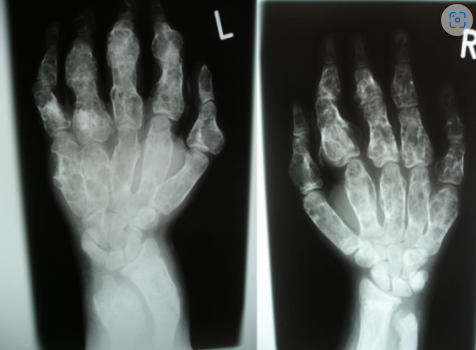

_____ shows eccentric well-lobulated lesions and sclerotic scalloped borders.

Hint: Bone tumor